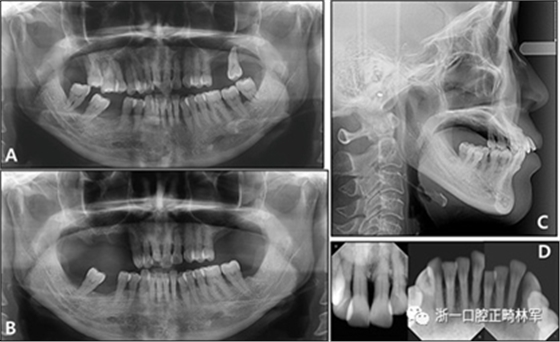

全景X線片顯示了牙槽骨支持的整體下降和下頜左側側切牙區(qū)廣泛的骨質喪失。頭影測量分析表明是具有正常垂直面形,上頜切牙唇向錯位以及與Rickett‘s E線相關的上唇前凸的骨性I類關系(圖3和4;表II)?;颊弑辉\斷為骨骼I類錯合畸形,伴有慢性中度牙周炎和多顆牙齒缺失。

圖3. 治療前X線片:A,牙周治療前的全景X光片; B,牙周治療后的全景X光片; C,側位X線片; D,根尖片。

圖4. 治療前的投影測量